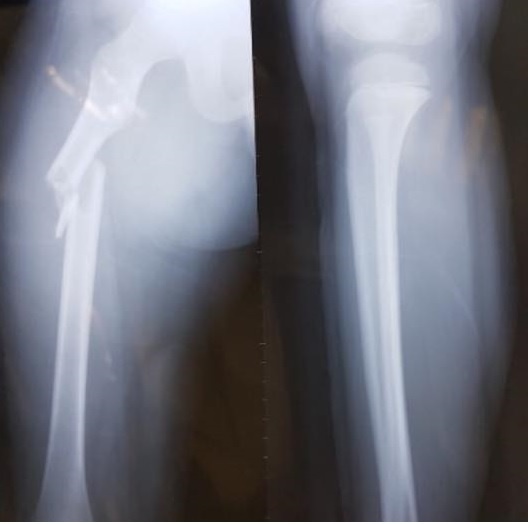

| Hình ảnh khi xương đùi của học sinh Trần Chí Kiên được chụp X-quang. Ảnh: NVCC.

Sự việc bắt đầu vào ngày 1/12/2016, em Trần Chí Kiên bị ngã gãy xương đùi tại trường Tiểu học Nam Trung Yên.